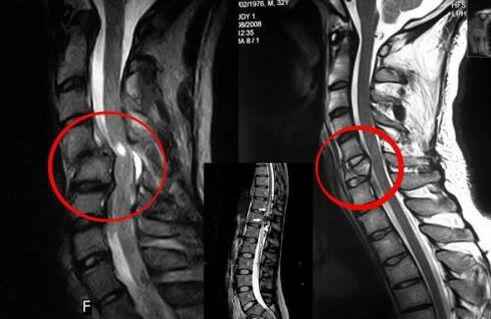

Diagnostic

L'ostéochondrose vertébrale nécessite une consultation rapide avec un médecin qui aidera à restaurer le dos endommagé. Les équipements modernes permettent de poser un diagnostic dès les premiers stades de développement. En cas de pathologie, contactez un neurologue ou un orthopédiste. Tout d'abord, un examen de la colonne vertébrale blessée est effectué et un historique médical est effectué, puis des méthodes de diagnostic en laboratoire et instrumentales sont prescrites pour identifier l'ostéochondrose :

- Radiographie ;

- myélographie;

- examen neurologique;

- TDM et IRM ;

- résonance magnétique nucléaire.